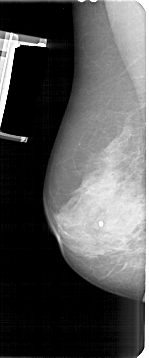

A_1683_1.LEFT_MLO

LEFT_MLO LINES 5356 PIXELS_PER_LINE 2221 BITS_PER_PIXEL 12 RESOLUTION 43.5 NON_OVERLAY